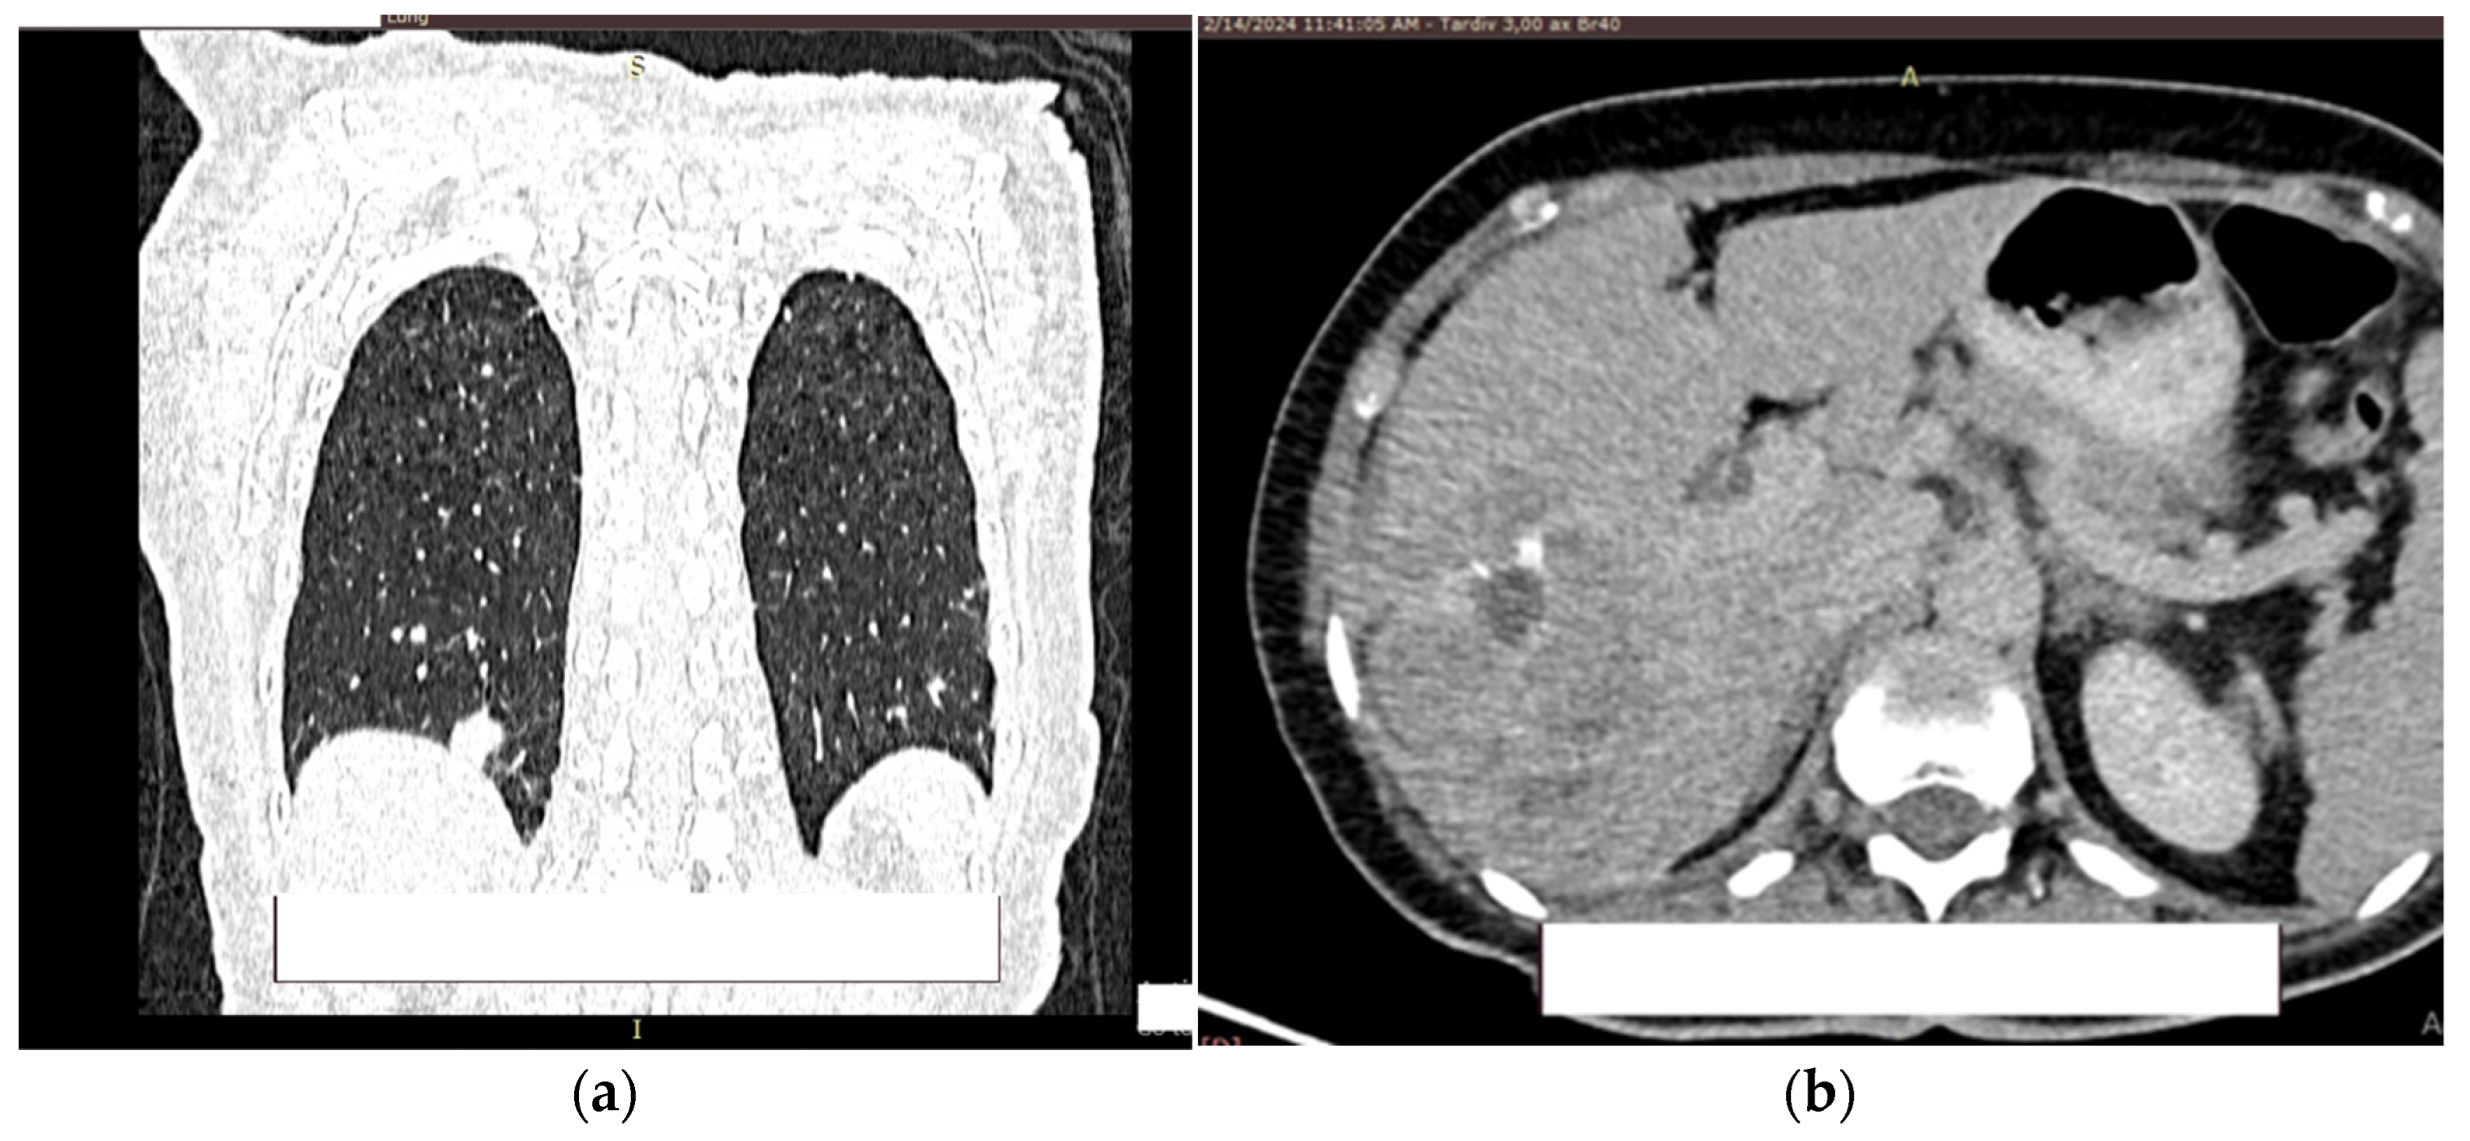

At the level of the pulmonary parenchyma, the CT examination shows multiple pulmonary nodules distributed diffusely, bilaterally with a metastases CT aspect, the largest located in the posterobasal part of the right lung with a 14 mm diameter (Figure 8a).

No solid tumor masses were observed in the digestive tract; only intestinal fluid stasis and some hydroaeric levels were present. At the level of the right lobe of the liver, a poly nodular conglomerate with a 98/68 mm maximum diameter in the coronal plane, natively hypodense nodules and postcontrast with the presence of metal clips from the previous liver surgery (Figure 8b). It was unclear whether this finding represents a secondary liver lesion or is a result of the previous liver metastasectomy.

Figure 8. Contrast CT aspect. If there are multiple panels, they should be listed as: (a) Description of what is contained in the first panel; (b) Description of what is contained in the second panel. Figures should be placed in the main text near to the first time they are cited.